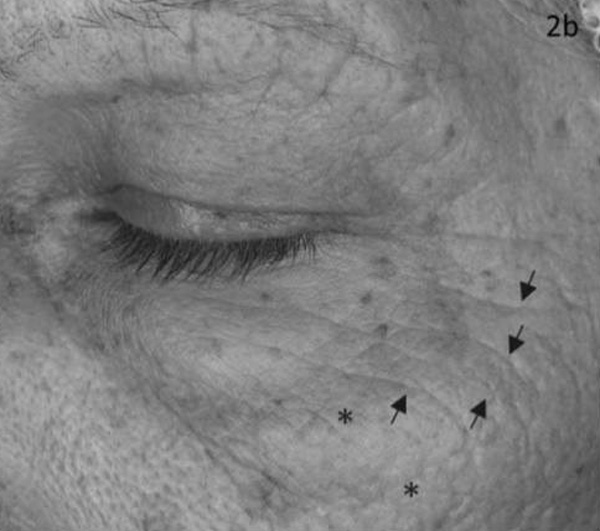

На фотографиях представлены два пациента, фотографии сделаны до (слева) и после приема добавки Q10 (справа). Стрелки указывают на уменьшение морщин. По мнению дерматологов, Q10 сделал кожу мягче и уменьшил количество мелких морщин.